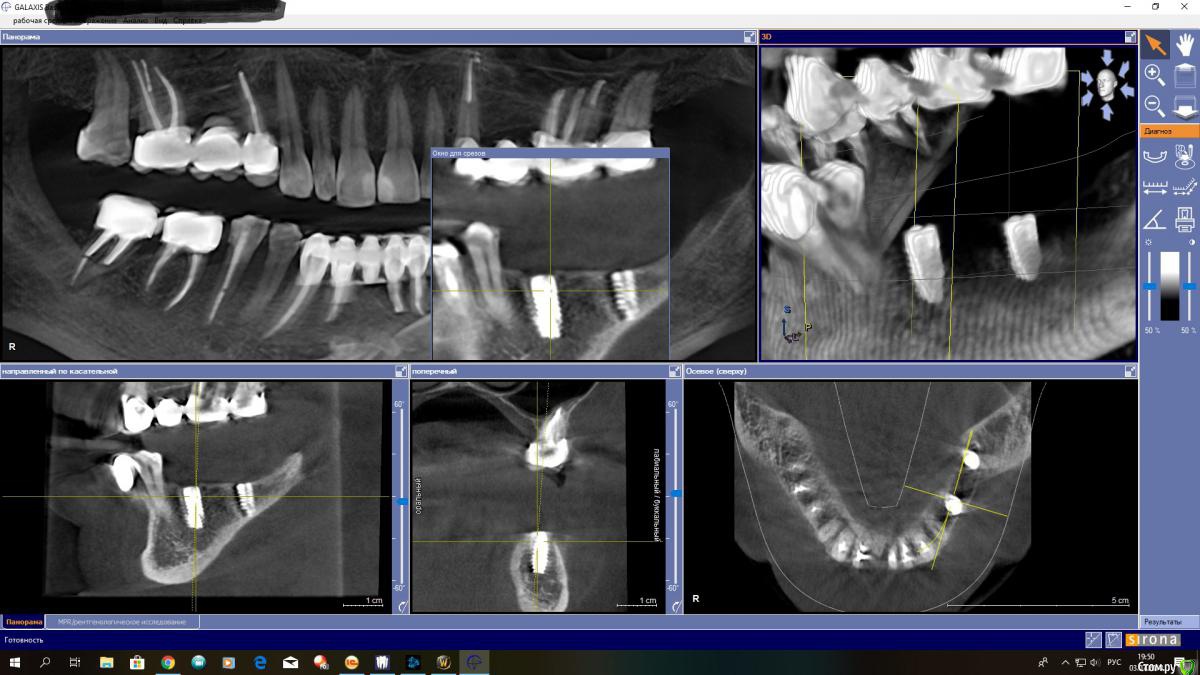

Ponchik Опубликовано 3 июля, 2018 Поделиться Опубликовано 3 июля, 2018 Вот как-то так блин получилось Весь из себя психованный ставил (дома поругался), а может по жизни косорукий, и вот.... язычная стенка 0.5-0.75 При запиле и вкручивании язычная стенка вела себя хорошо. Видел её язычно на 5-6мм вниз точно.Опыта мало, не знаю как поступить. Может вызвать пациентку и выкрутить его ? Ссылка на комментарий

TIGER Опубликовано 3 июля, 2018 Поделиться Опубликовано 3 июля, 2018 1.jpg Вот как-то так блин получилось Весь из себя психованный ставил (дома поругался), а может по жизни косорукий, и вот.... язычная стенка 0.5-0.75 При запиле и вкручивании язычная стенка вела себя хорошо. Видел её язычно на 5-6мм вниз точно.Опыта мало, не знаю как поступить. Может вызвать пациентку и выкрутить его ?БУДЕТ жить,не переживайте Ссылка на комментарий

Ponchik Опубликовано 3 июля, 2018 Автор Поделиться Опубликовано 3 июля, 2018 (изменено) https://photos.google.com/photo/AF1QipPJXDLEMrh16Or_6JOOJ6cuWlvGx85mMav8Tow_ Ссылка на "прокрутку КТ" 17сек. видео Изменено 3 июля, 2018 пользователем Ponchik Ссылка на комментарий

Ethan Hunt Опубликовано 4 июля, 2018 Поделиться Опубликовано 4 июля, 2018 я бы выкрутил в тот же момент. В области этого зуба, как правило, необходима ангуляция в пределах до 20 градусов. Нагрузите имплантат - может пойти резорбция язычно. Может и не пойти...выбирать вам Ссылка на комментарий

Реваз Опубликовано 4 июля, 2018 Поделиться Опубликовано 4 июля, 2018 лучше конечно выкрутить, вероятность резорбции большая Ссылка на комментарий

Тимур86 Опубликовано 4 июля, 2018 Поделиться Опубликовано 4 июля, 2018 (изменено) Вообще проблемы не вижу. Как и раньше говорил-если после всех имплантов все КТ будут делать,то устанем имланты выкручивать))десны добавить и всё хорошо будет Изменено 4 июля, 2018 пользователем Тимур86 5 Ссылка на комментарий